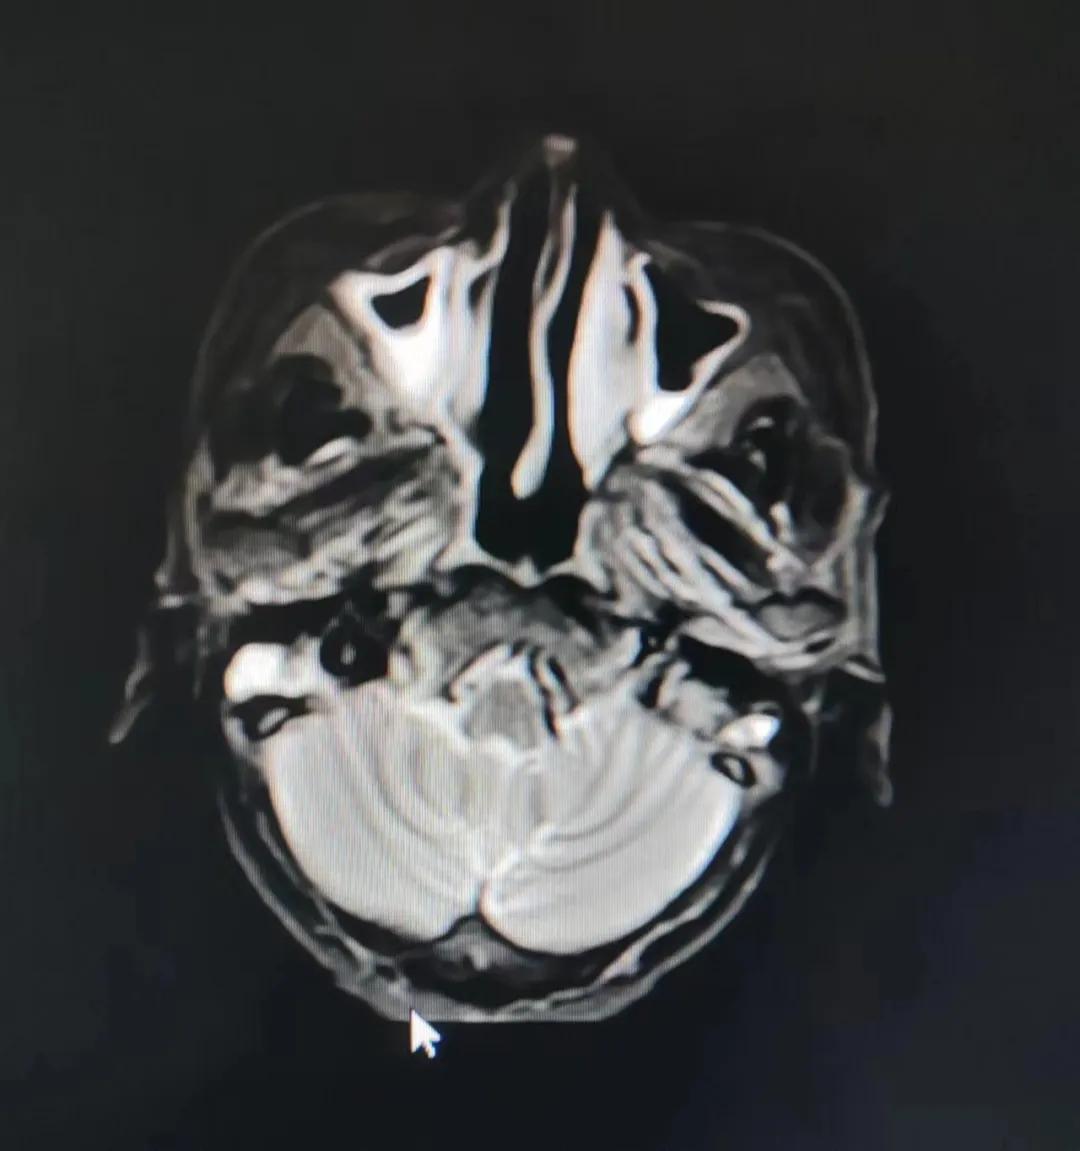

治療前

考慮到患者年齡較大、體質(zhì)差,手術(shù)難度大,且常規(guī)的放射治療難以保護(hù)患者晶體造成患者雙眼視力損傷,放療團(tuán)隊(duì)以最快的速度制定了精準(zhǔn)放射治療方案并開始為其實(shí)施治療。僅僅數(shù)日后,老人腫塊出血即得到控制,腫塊明顯縮小,放療20次后腫塊迅速縮?。?/div>